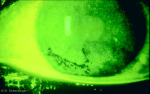

Kératite ponctuée centrale et périphérique de grade 3, confluente à 4 heures